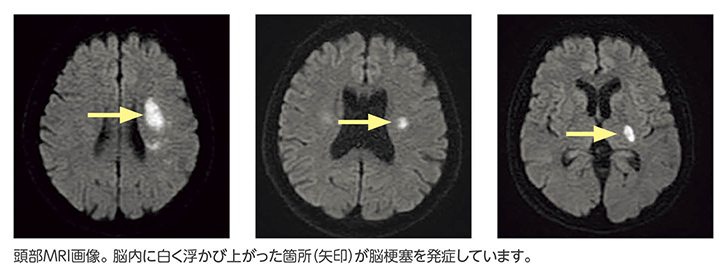

突然の神経脱落症状(片麻痺・失語・構音障害など)を来した場合、頭部の画像検査を実施します。特に発症早期の脳梗塞については、頭部CTよりも頭部MRIでの診断がより正確であるため、当院では頭部MRIを中心に脳梗塞の検査を行っています。MRIで脳梗塞が確認された場合は、前記したの3つの脳梗塞のうち、いずれのパターンに入るのかを頭部や頸部血管、心電図などをもとに判断し、それぞれに応じた再発予防の薬剤を決定します。ただし、脳梗塞は一度起きてしまうと回復しにくい病気であるため、先にも述べましたがまずは発生させないように予防することが非常に重要です。